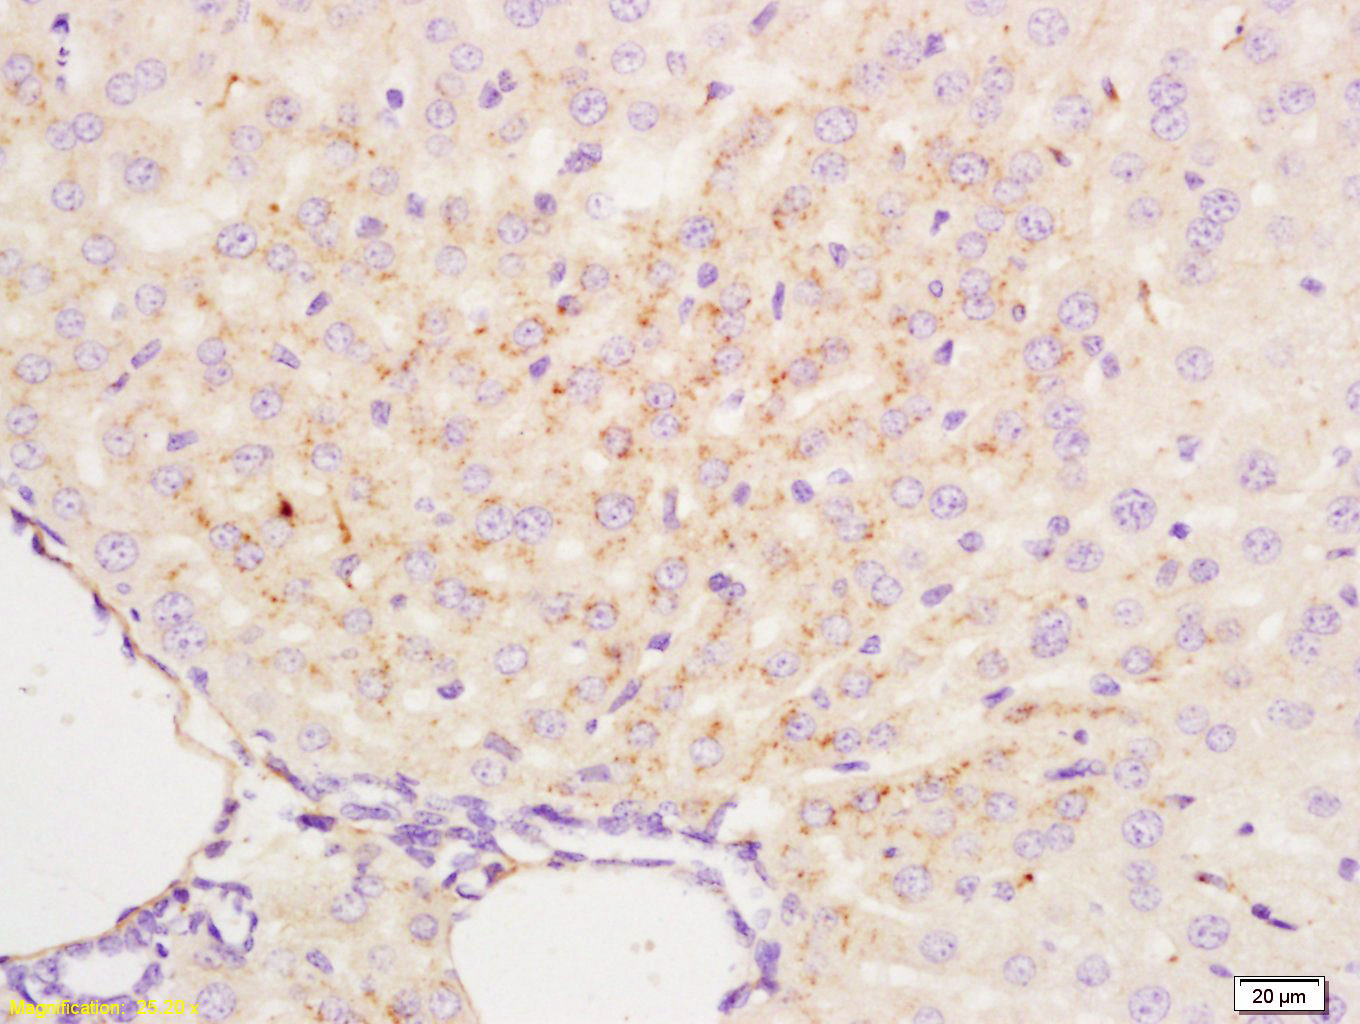

Paraformaldehyde-fixed, paraffin embedded (Rat brain); Antigen retrieval by boiling in sodium citrate buffer (pH6.0) for 15min; Block endogenous peroxidase by 3% hydrogen peroxide for 20 minutes; Blocking buffer (normal goat serum) at 37°C for 30min; Antibody incubation with (APG4B) Polyclonal Antibody, Unconjugated (bs-1384R) at 1:400 overnight at 4°C, followed by operating according to SP Kit(Rabbit) (sp-0023) instructions and DAB staining.

Tissue/cell: mouse liver tissue; 4% Paraformaldehyde-fixed and paraffin-embedded; Antigen retrieval: citrate buffer ( 0.01M, pH 6.0 ), Boiling bathing for 15min; Block endogenous peroxidase by 3% Hydrogen peroxide for 30min; Blocking buffer (normal goat serum,C-0005) at 37℃ for 20 min; Incubation: Anti-APG4B/AUTL1 Polyclonal Antibody, Unconjugated(bs-1384R) 1:200, overnight at 4°C, followed by conjugation to the secondary antibody(SP-0023) and DAB(C-0010) staining